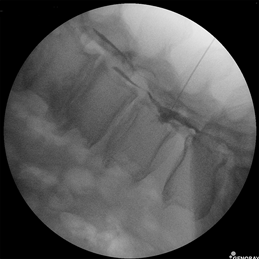

본원에서는 주로 많이 시행되는 신경차단술이나 인대증식치료를 초음파나 C-arm(영상장치)을 통해 안전하고 정확한 시술을 합니다.

2005년도부터 우리나라 의료계에선 선구적으로 근골격계 초음파유도 중재시술과 C-arm(영상장치)중재시술을 시행하여 정확한 진단과 안전하고 효과적인 치료를 위해 많은 노력을 기울였습니다.

실시간 영상장치인 C-arm 장치로 직접 눈으로 확인하며 주사바늘이 달린 지름1mm, 길이 45cm의 카테터를 꼬리뼈를 통해 척추의 경막외공간내로 삽입하여 디스크나 협착증이 신경을 압박하고 있는 부위까지 정확히 도달합니다. 카테터 끝을 이용하여 유착을 풀고 유착방지효소제와 항염증제를 주입해 통증을 유발하는 염증과 부종, 신경주위의 유착을 치료하는 시술입니다.